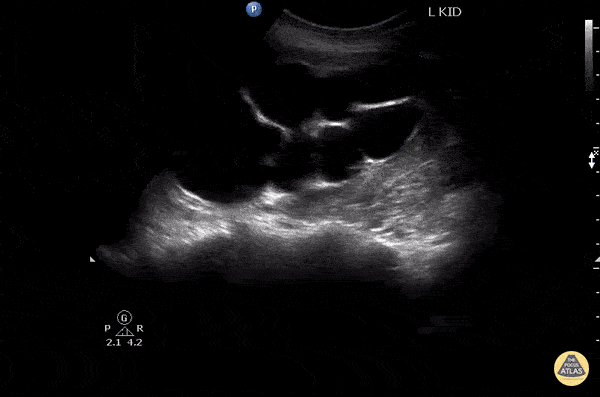

Renal/GU - Severe Hydronephrosis vs Cyst?

This is a long axis image of severe hydronephrosis that mimics a cystic kidney. Image courtesy of Robert Jones DO, FACEP @RJonesSonoEM Director, Emergency Ultrasound; MetroHealth Medical Center; Professor, Case Western Reserve Medical School, Cleveland, OH View his original post here